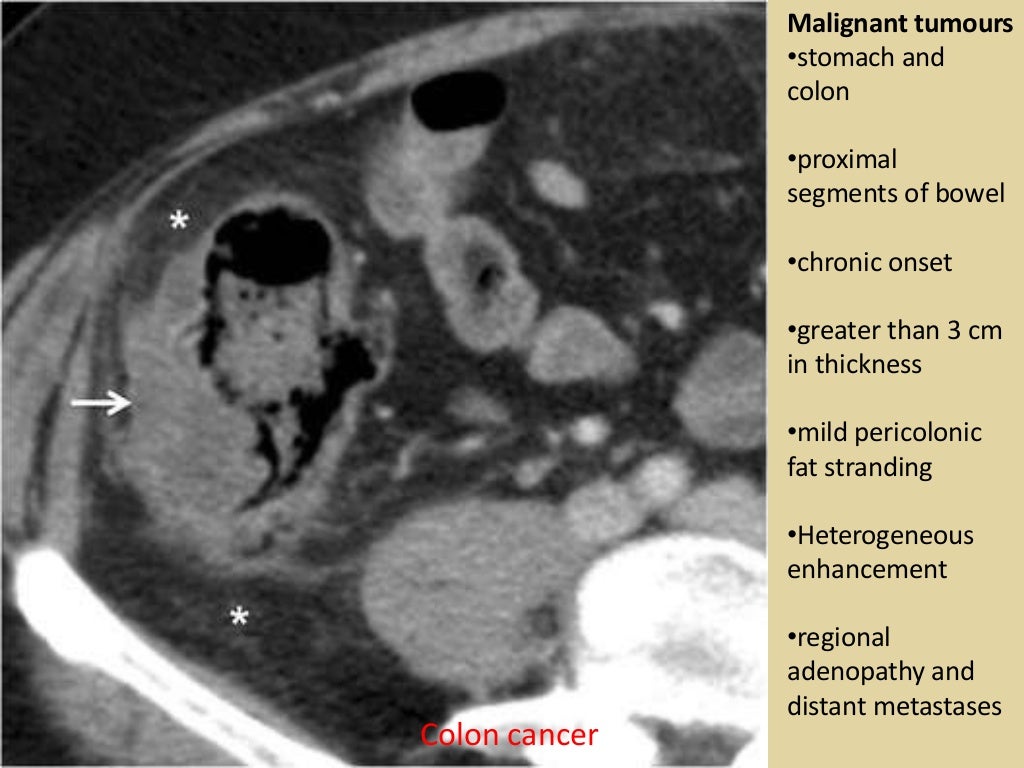

CT scan demonstrating wall thickening colorectal cancer (CRC) of the What Is Thickening Of The Colon Wall Mean Thickening of the small or large bowel wall may be caused by neoplastic,. Bowel wall thickening can be seen through thickening of the valvulae conniventes (small bowel) or haustral folds (colon) the true thickness of the bowel wall. Advances in technology and accumulated. • thickening of the bowel wall may be focal (40 cm) in extension. Bowel wall thickening is. What Is Thickening Of The Colon Wall Mean.